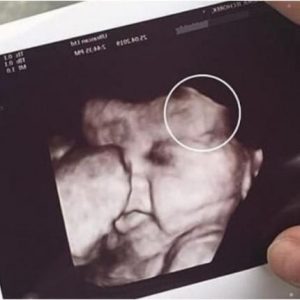

Mother is scared to see her daughter’s ultrasound; image showed the… See more

A routine prenatal checkup took an unexpected turn for one mother after she grew visibly anxious during her daughter’s ultrasound appointment. According to witnesses at the clinic,…